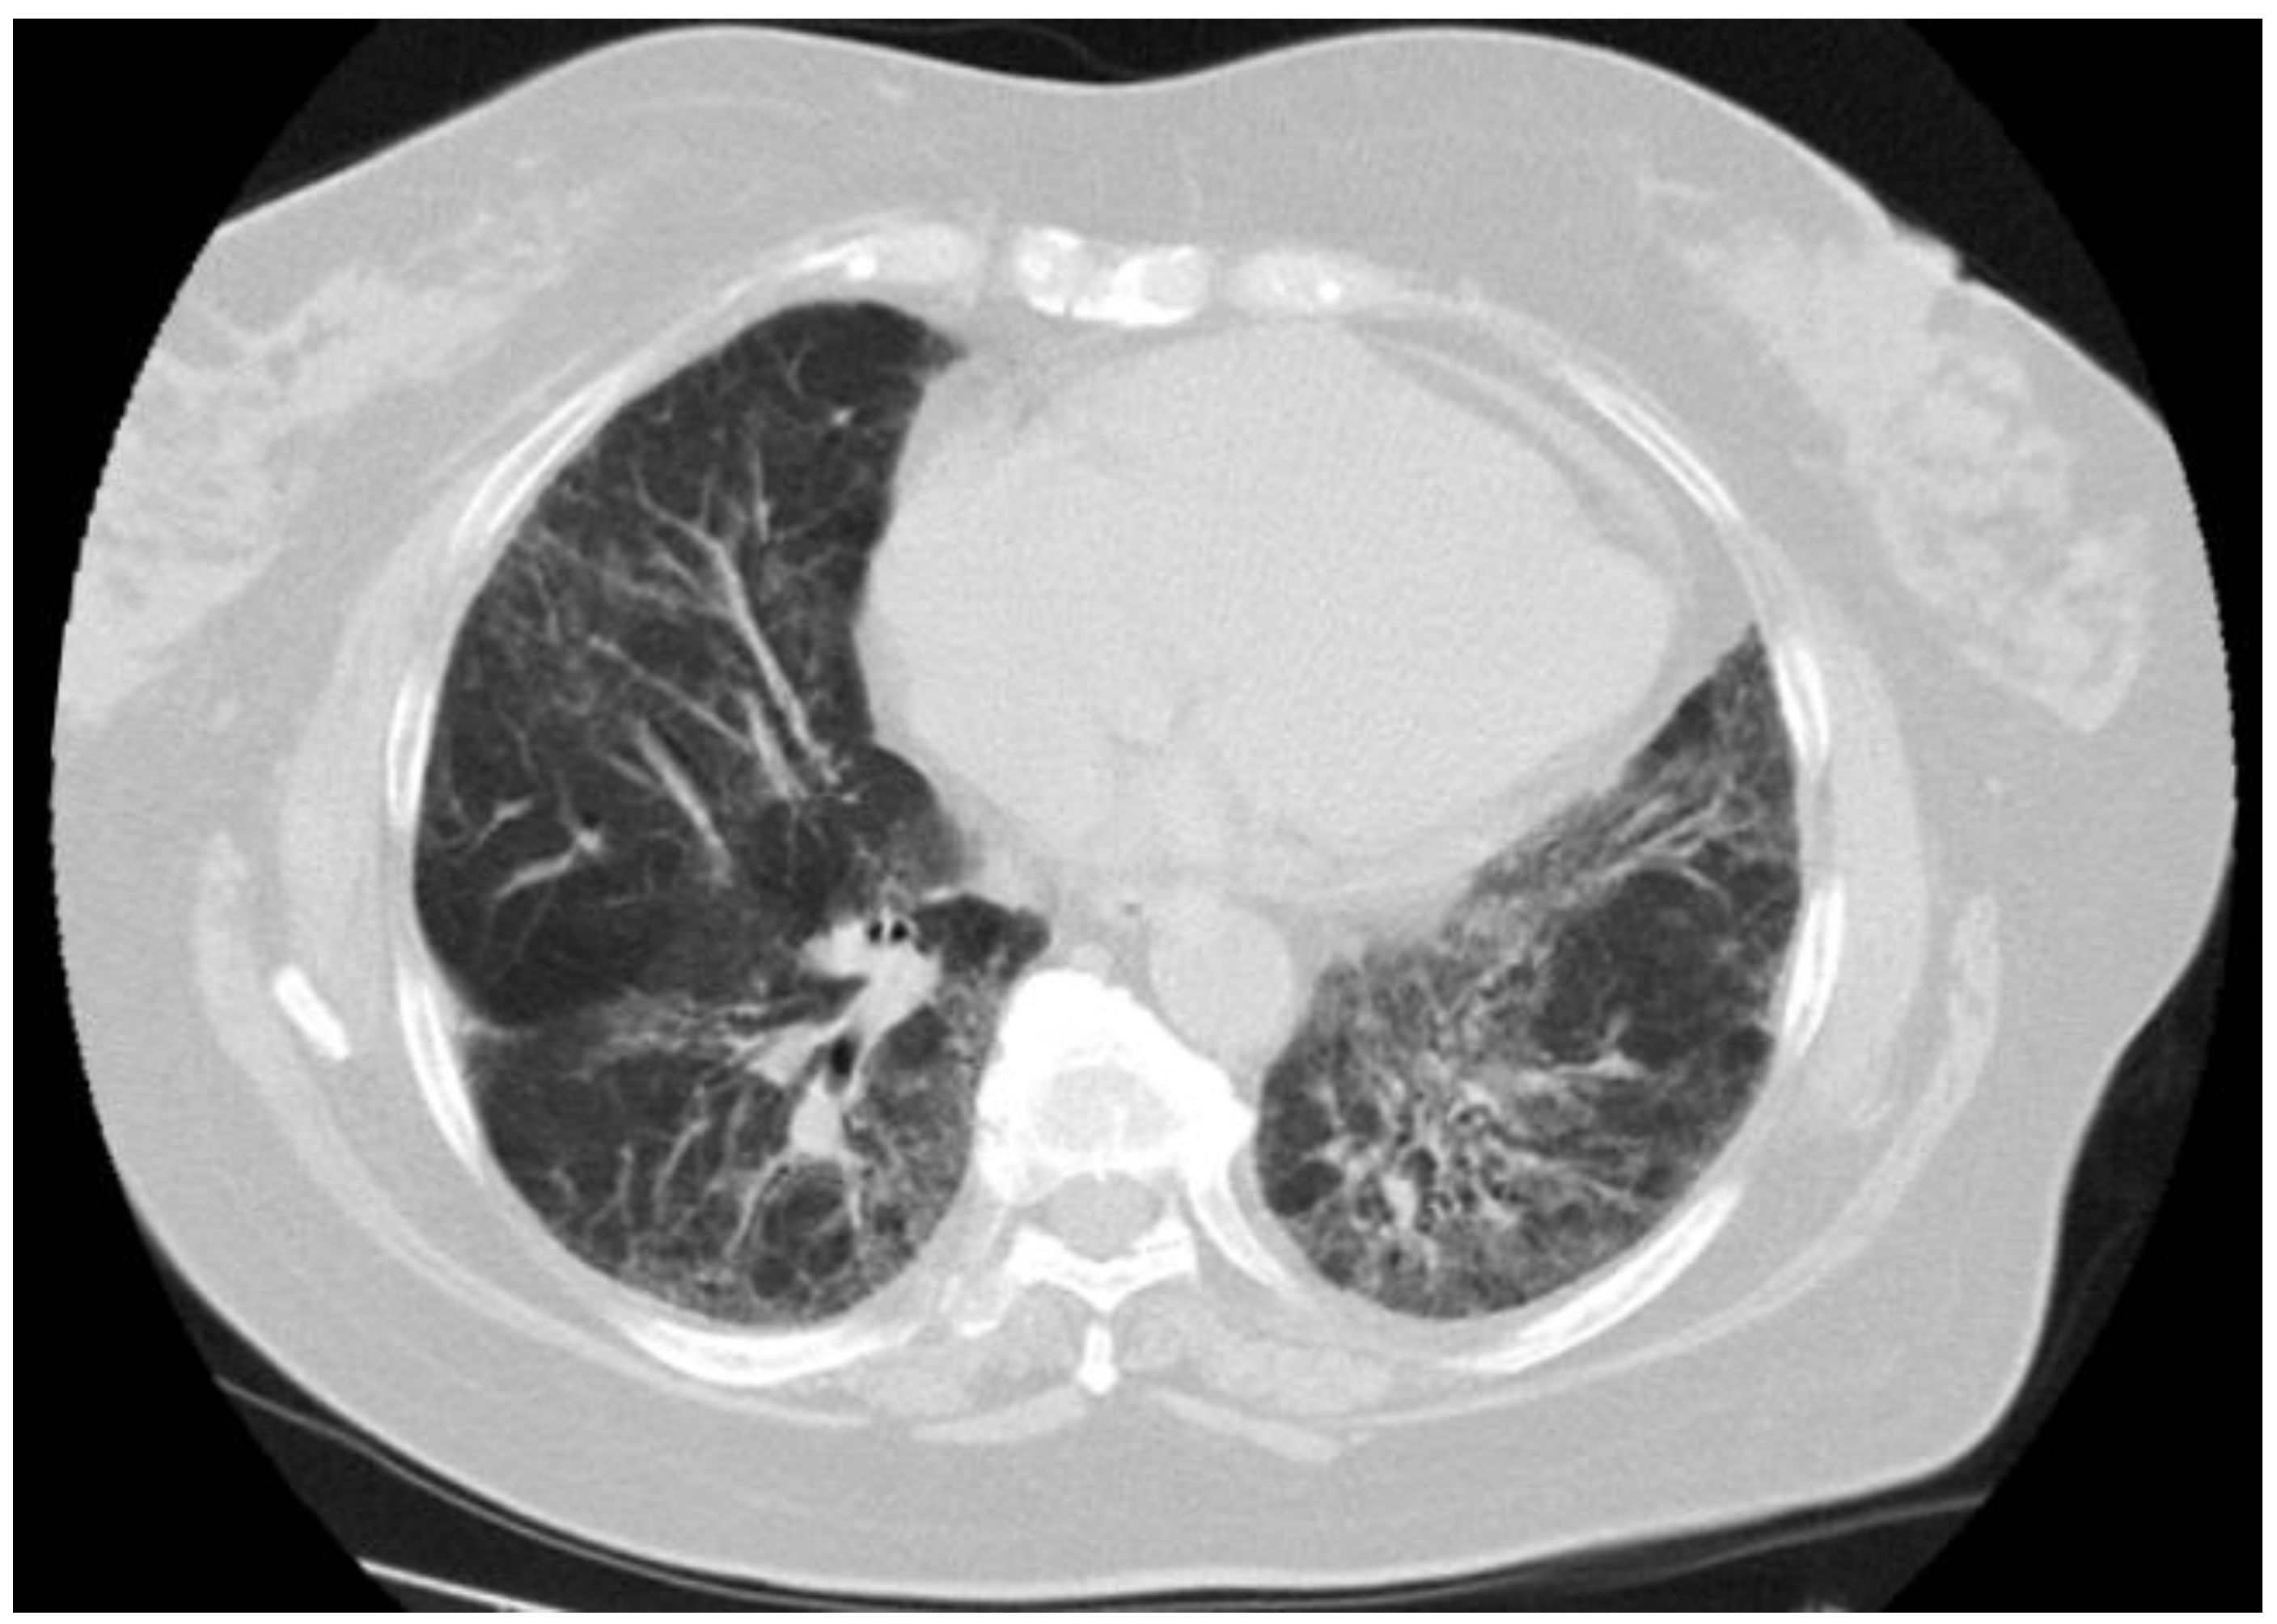

Figure 2.

NSIP pattern in a 70-year-old female with PBC who died from progressive respiratory failure.